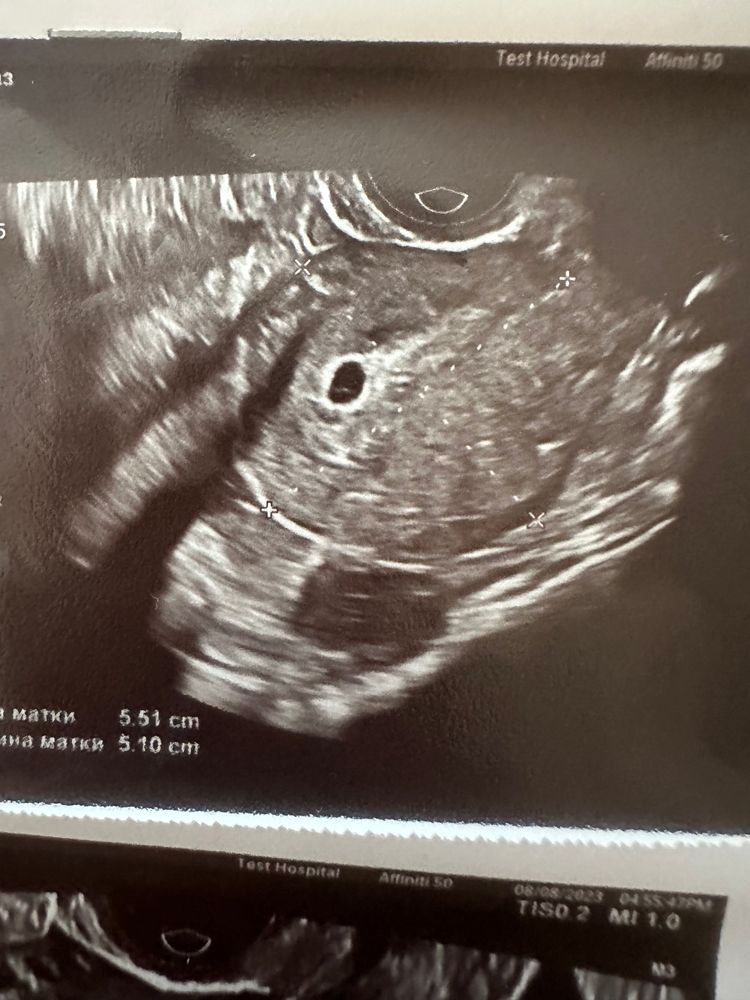

Ксения, спасибо . Сходила сделала в другом месте . Вот что увидели . Изображение Это же эмбрион ? Который вот вот разовьется

Диана, Изображение Вот пер Изображение Вот первое узи , видно точку

Сабрина, Изображение Изображение А вот узи сегодняшнее

Мама ангелочка и дочек, 1,7

Мама ангелочка и дочек, может эьо желточный мешок, а не эмбрион и вы напутали.

Мама ангелочка и дочек, а он разве мог пропасть ? напутала не я , получается, а узист